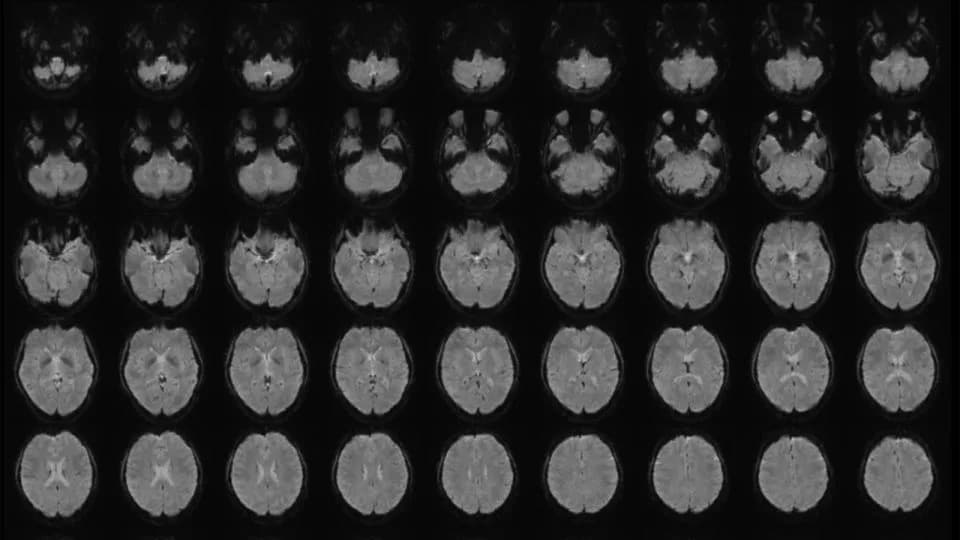

Uređaji koji 'čitaju' mozak: tehnološki proboj i ozbiljna pretnja privatnosti

BCI i EEG uređaji sve preciznije prevode moždane signale u komande i podatke. AI poboljšava dekodiranje i omogućava detekciju pred‑svesnih namera, ali to otvara velike rizike za privatnost i autonomiju korisnik...